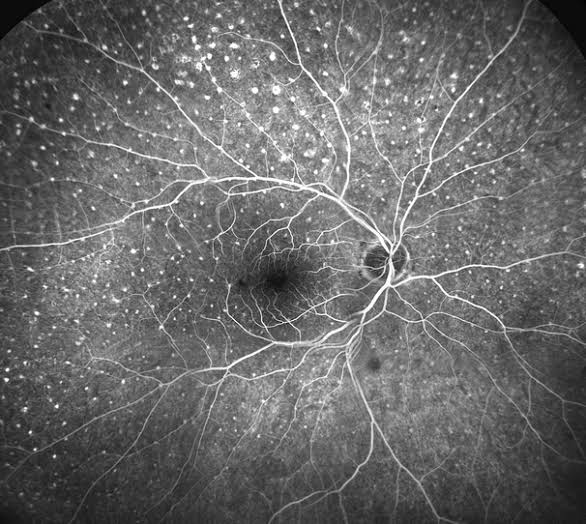

Au sein de notre service d’Angiographie, vous prendrez en charge nos patients de l’arrivée dans le service à la fin de l’examen dans le respect de leur intégrité et leurs besoins. Votre travail sera à réaliser des procédures angiographiques en collaboration avec nos médecins dans le respect des protocoles en vigueur et des règles d’hygiène. Dans le cadre de cette activité, vous aurez des astreintes à effectuer.